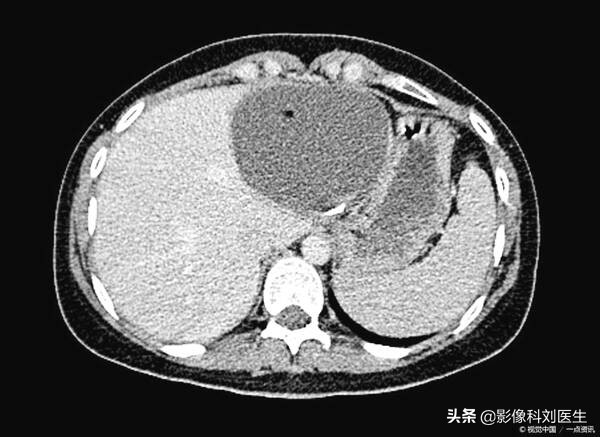

2、CT检查。CT平扫一般显示为肝实质内圆形的低密度影,边缘锐利,境界清楚,囊内密度均匀,一般CT值约0-20HU。增强扫描后病灶没有明显强化,在周围强化的肝实质的衬托下,囊肿边界更加清晰。